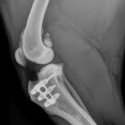

Wij komen regelmatig afwijkingen en ziekten van het steun- en bewegingsapparaat tegen. Ziekten aan het bewegingsapparaat worden vaak gekenmerkt door pijn; dieren komen niet overeind, bewegen minder of kunnen kreupel lopen. Soms is het noodzakelijk om röntgenfoto’s te maken om de oorzaak van de kreupelheid op te sporen. Hiervoor beschikken wij over een digitaal apparaat. Indien nodig kunnen röntgenfoto’s gemakkelijk met specialisten overlegd worden.

Vaak zal een bewegingsadvies gecombineerd met geschikte medicatie een oplossing bieden. In sommige gevallen zal een operatie noodzakelijk zijn om de klachten te verhelpen.